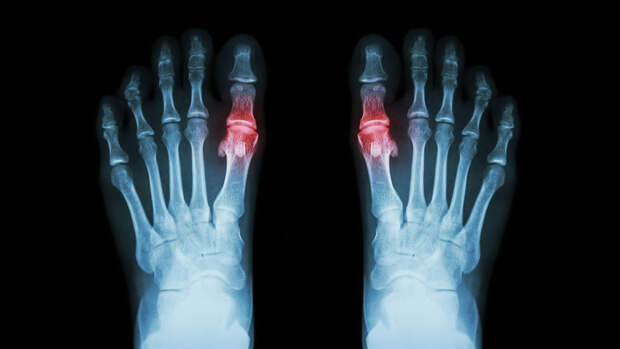

Подагра — форма воспалительного артрита. При этом заболевании происходит накопление мочевой кислоты в крови и образование кристаллов моноурата натрия. Эти кристаллы откладываются в суставах, вызывая воспаление и сильную боль. Поскольку это наблюдательное исследование, причина выявленной связи остается неизвестной.